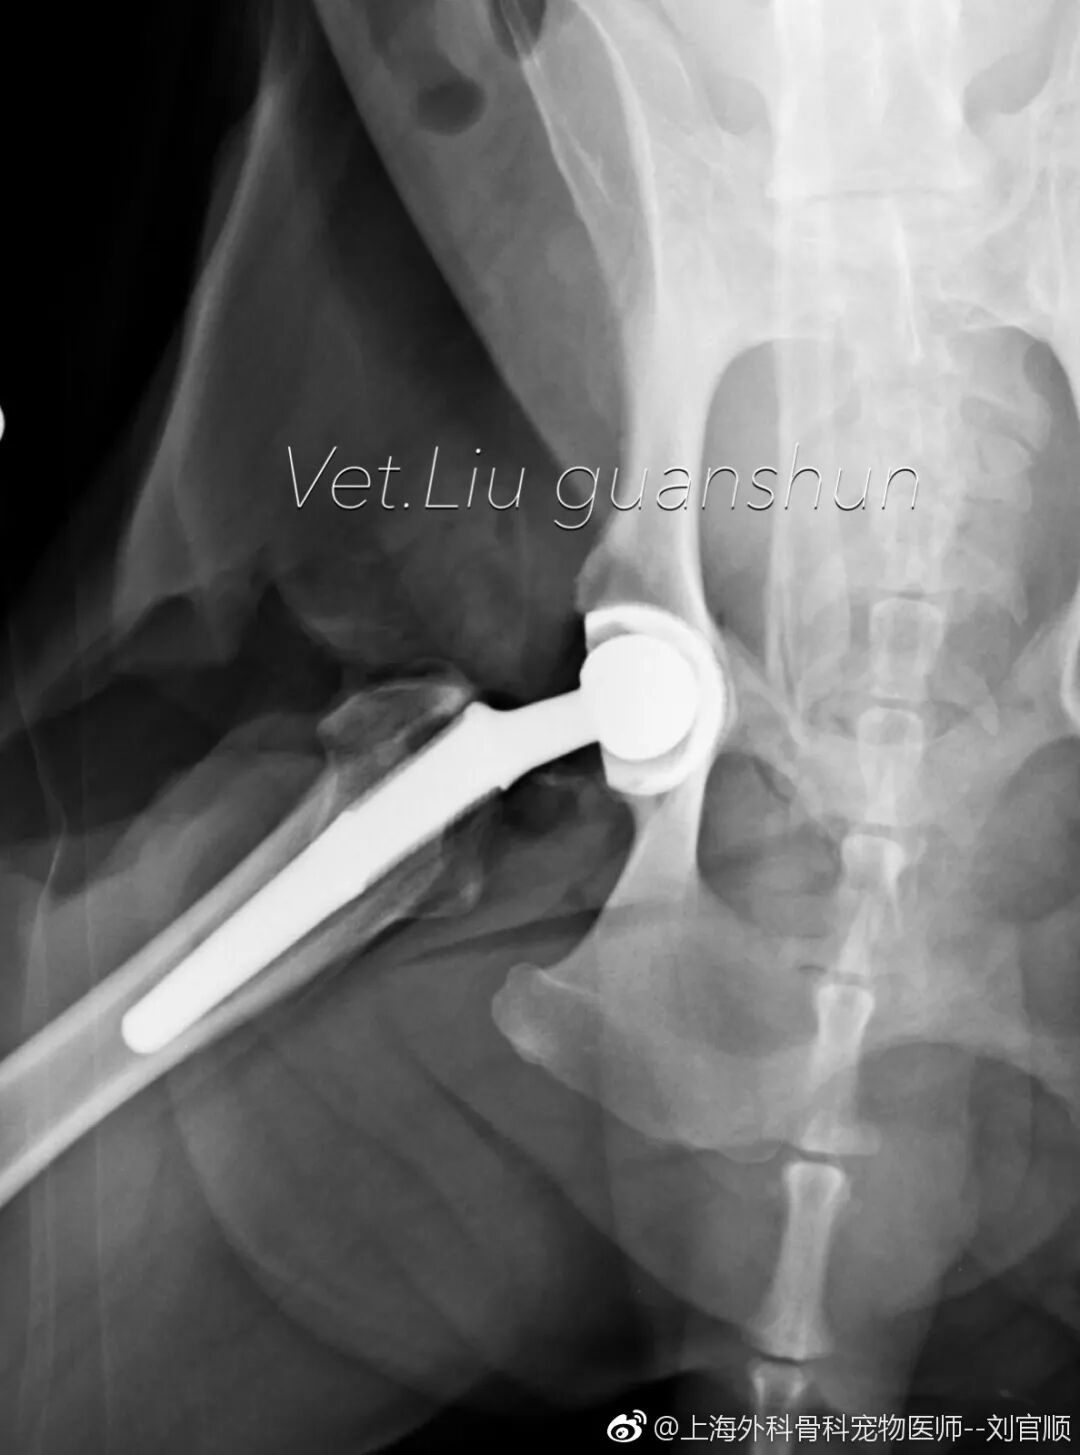

外科专科、骨科专科、心脏病门诊、髋关节置换、前十字韧带手术等

髋关节置换手术后第三天,出来活动活动!

中国取得BioMedtrix全髋置换全部认证的只有两位兽医师